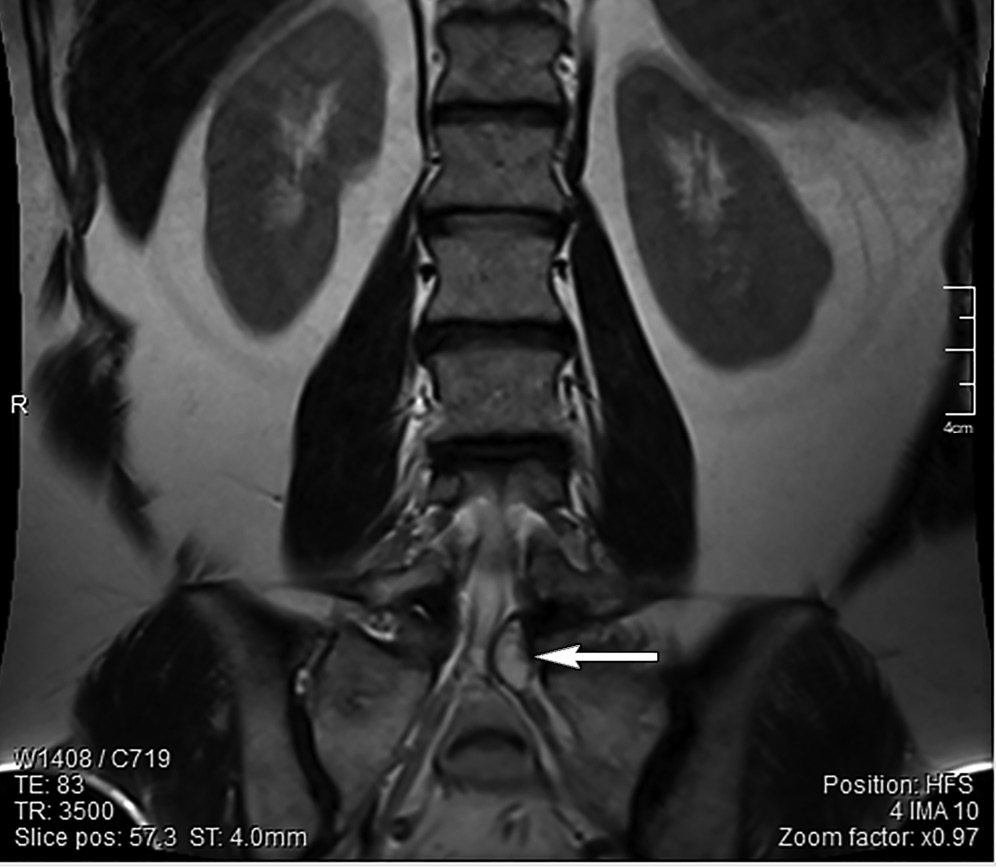

МРТ поясничного отдела позвоночника (рис. 1, 2): дегенеративно-дистрофические изменения пояснично-крестцового отдела позвоночника — 3-й период. Позвоночный канал деформирован на уровне LV-SI слева с сужением резервного эпидурального пространства и стенозированием левых латеральных отделов позвоночного канала на ширину до 0,3 см. Слева в промежутке LV-SI визуализируется образование с ровными четкими контурами, гиперинтенсивного сигнала в Т2и гипоинтенсивного сигнала в Т1-режимах, размером 14×8×8,5 мм. Прослеживается связь образования с дугоотростчатым суставом. Киста пролабирует из полости сустава в позвоночный канал по левому боковому карману, приводя к стенозу и компрессии спинномозговых корешков на уровне LV-SI.

Рис. 2. Пациентка С.: МРТ поясничного отдела позвоночника во фронтальной проекции на уровне межпозвонкового диска LV-SI слева. Визуализируется киста фасеточного сустава в проекции спинномозгового корешка SI (стрелка)

Важно отметить, что на фронтальных МРТ-сканах периартикулярная киста компримирует спинномозговой корешок SI. Прослеживается расположение кисты в латеральном канале, где отмечается щелевидная полость, которая сообщается с полостью фасеточного сустава.